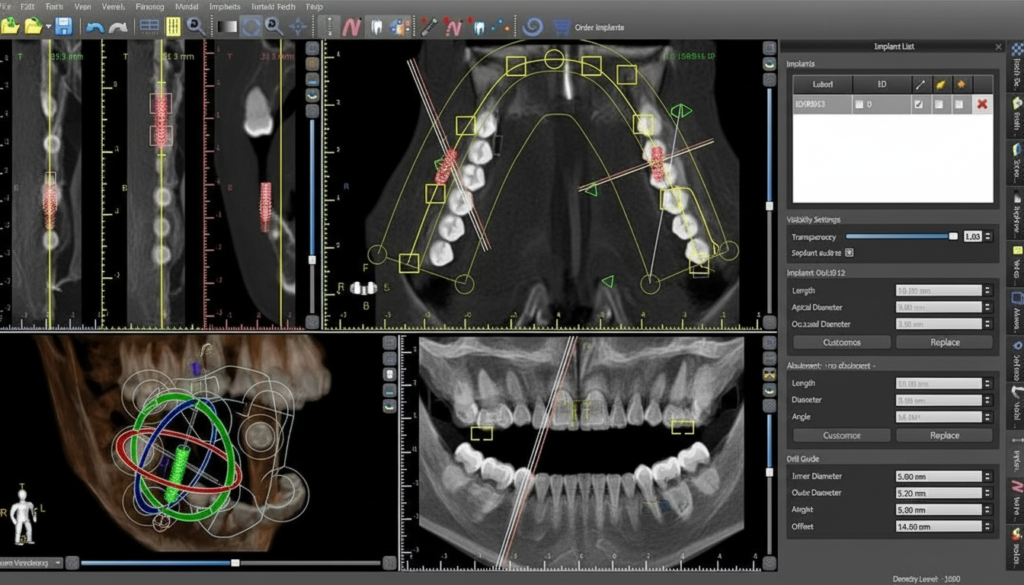

シミュレーションソフト

CTスキャンで取得した詳細なデータをコンピュータに取り込み、専用のシミュレーションソフトで綿密に解析します。

この解析により、インプラントの最適な大きさ、正確な埋入位置、適切な埋入角度を判断し、術前に具体的な手術計画を立てます。

2つの3Dシミュレーション

2つの3Dシミュレーションソフトを使用し、多角的、立体的に準備を進めます。当院では、経験豊富な設計のプロと一緒に万全のインプラント設計計画を立てており、可能な限り事前に患者様への不安と取り除くよう努めております。